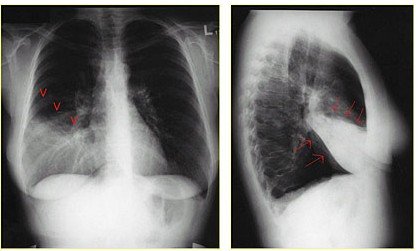

3. 胸部X线检查(下图):

早期:纹理模糊

实变:叶或段分布密度均匀的致密影

完全消散约3周左右